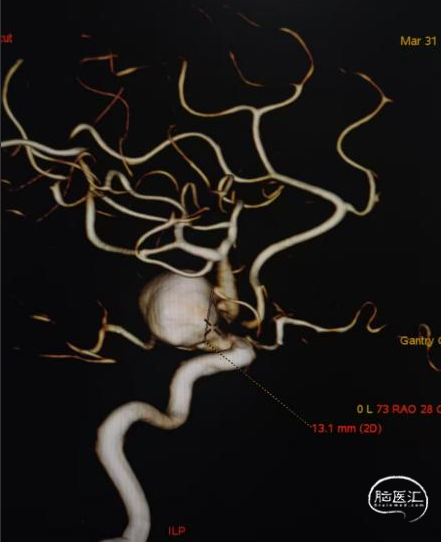

术前影像

脑动脉DSA提示右侧颈内动脉C5床突段动脉瘤。

右侧床突段载瘤动脉远端血管直径为1.8mm,载瘤动脉近端血管直径为5.2mm,瘤体宽13.1mm,瘤体最大宽度21.8mm。